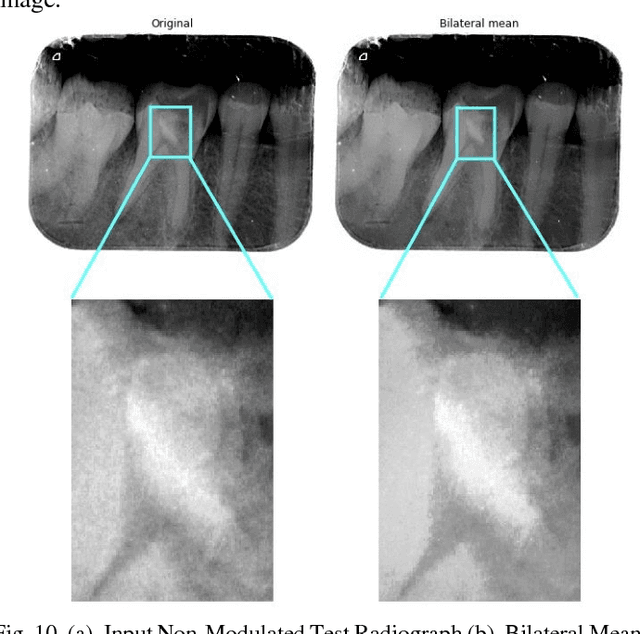

With the recent advancements in Image Processing Techniques and development of new robust computer vision algorithms, new areas of research within Medical Diagnosis and Biomedical Engineering are picking up pace. This paper provides a comprehensive in-depth case study of Image Processing, Feature Extraction and Analysis of Apical Periodontitis diagnostic cases in IOPA (Intra Oral Peri-Apical) Radiographs, a common case in oral diagnostic pipeline. This paper provides a detailed analytical approach towards improving the diagnostic procedure with improved and faster results with higher accuracy targeting to eliminate True Negative and False Positive cases.